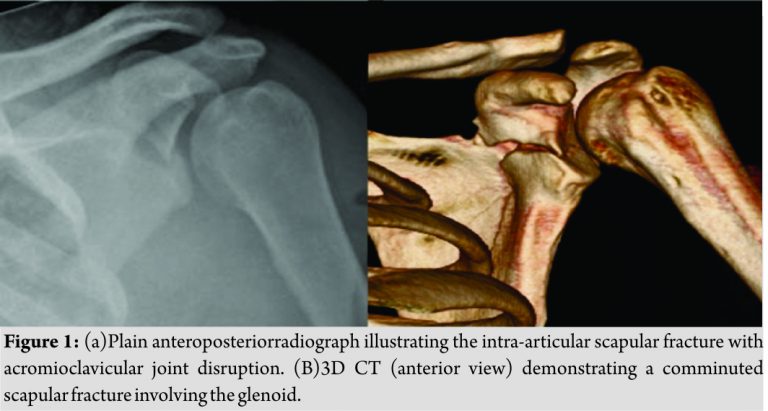

Neurovascular examination was unremarkable and no other injuries identified. Radiographs revealed anintra-articular fracture of the left scapula with disruption of the acromioclavicular joint (Fig. 1a). To help further assess the extent of injury, computed tomography with 3D reconstruction was performed which showed a comminuted fracture of the scapula involving the glenoid and body of the scapula (Fig. 1b). The patient underwent surgical fixation using a unique technique for repair of an intra-articular glenoid fracture with reduction of an associated acromioclavicular disruption.